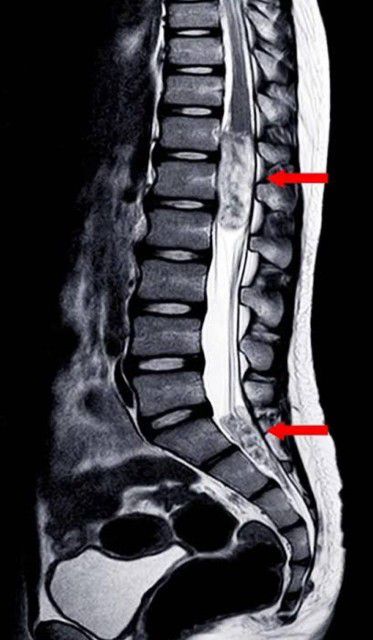

बिलासपुर-[जनहित न्यूज़] कमर एवं पीठ दर्द से पीड़ित एक 58 वर्षीय महिला जिसे दर्द निवारक दवा से भी आराम नहीं हो रहा था। अपोलो हॉस्पिटल बिलासपुर के न्यूरोसर्जरी विभाग में भर्ती हुई। भर्ती के समय ही महिला के दोनों पैरों में ताकत कम थी तथा उसका दैनिक दिनचर्या के प्रति सेंसेशन खत्म हो चुका था। अपोलो हॉस्पिटल बिलासपुर में उनकी एम आर आई जांच की गई। जांच में उनकी रीड की हड्डी के डी 1 डी 2 लेवल में स्पाइनल कॉर्ड का ट्यूमर पाया गया।

जांच करने के समय तक मरीज के दोनों पैरों की ताकत पूरी तरह चली गई थी एवं दैनिक दिनचर्या पर कंट्रोल भी खत्म हो चुका था। जांच की रिपोर्ट प्राप्त होते ही मरीज के परिजनों को काउंसलिंग कर न्यूरोसर्जन की टीम डॉक्टर सुनील शर्मा, डॉक्टर राजकुमार एवं डॉक्टर अरविंद कुमार के द्वारा माइक्रोस्कोप की सहायता से मरीज के स्पाइनल कार्ड के ट्यूमर का सफल ऑपरेशन किया गया।